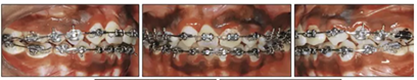

兩年半后,在上下牙弓上均實現(xiàn)了間隙關(guān)閉,并且使用0.017×0.025英寸的不銹鋼弓絲進行咬合精細調(diào)整(圖8)。去除托槽后,上下頜采用舌側(cè)弓進行保持(圖9)。